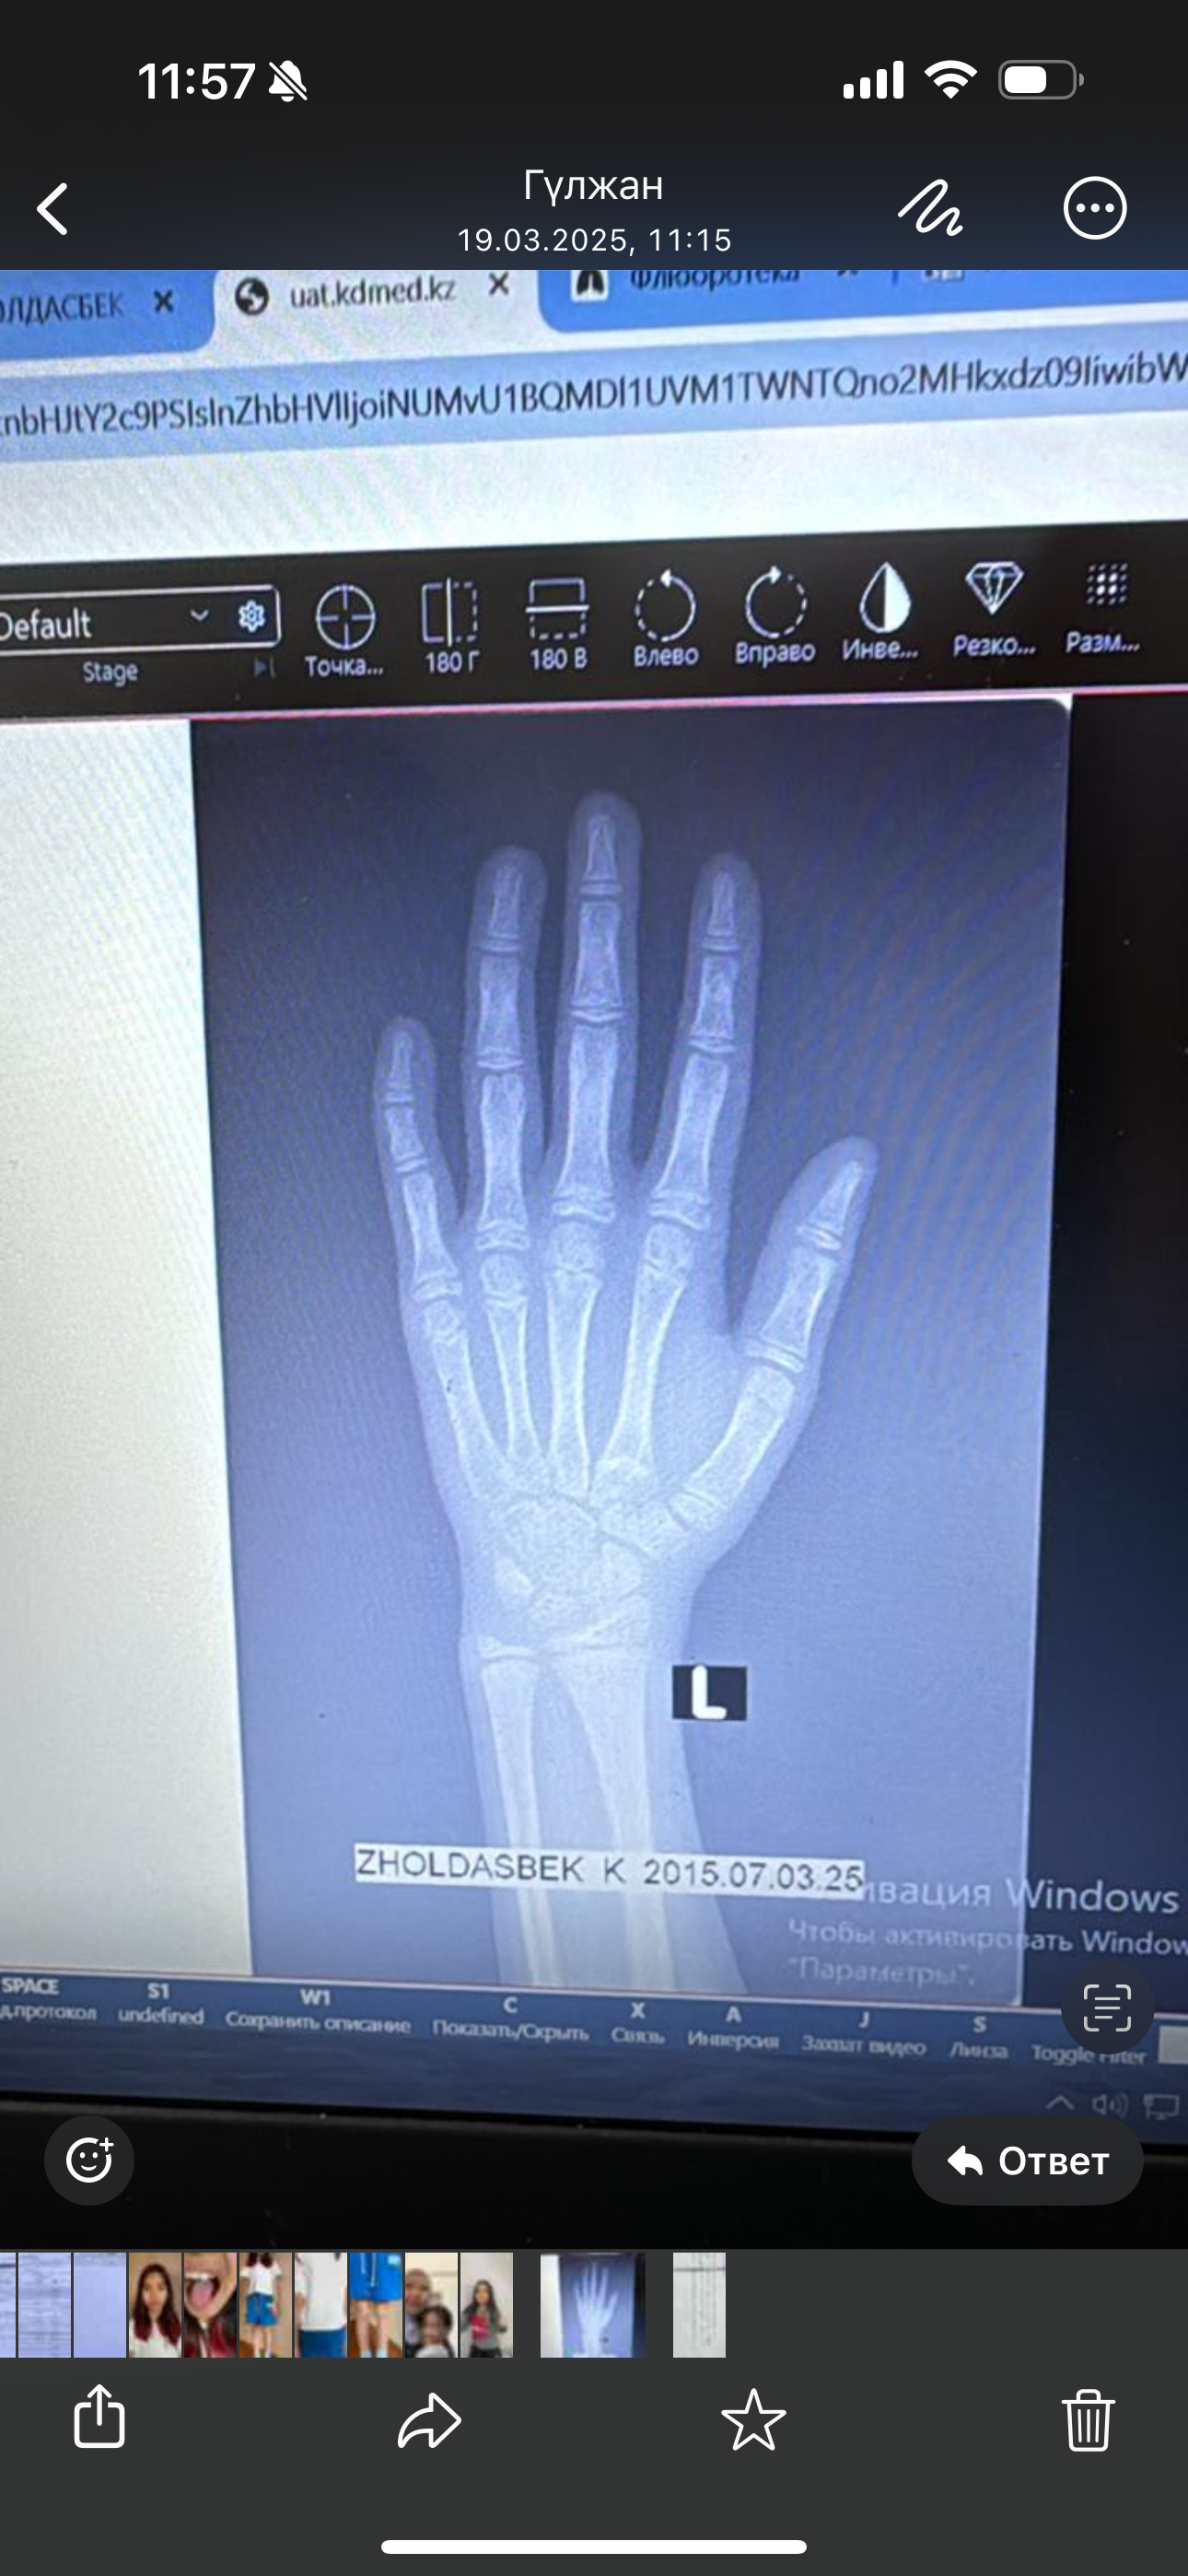

Здравствуйте, девочка,9,9 лет, помогите определить костный возраст. Зоны роста открыты? и на сколько лет вы оцениваете костный возраст ? Спасибо. Ср, 26/03/2025 - 00:20 #1 Дарья_Белявская Не на сайте Был на сайте: 8 месяцев 5 дней назад Зарегистрирован: 26.03.2025 - 00:09 Публикации: 2 По анализам : Вес - 20,0 кг, SDS веса (-3,01) соответсвует 6,6 годам Рост - 124,0 SDS роста (-2,03) соответсвует 8 годам ИМТ - 13,0, SDS имт (-2,48) Приложения:

Вес - 20,0 кг, SDS веса (-3,01) соответсвует 6,6 годам

Рост - 124,0 SDS роста (-2,03) соответсвует 8 годам

ИМТ - 13,0, SDS имт (-2,48)